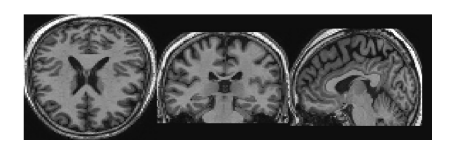

深度学习在医疗数据集上的第一个应用是医疗图像包括:MRI,CT,PET,X-ray,Microscopy,US,MG等。